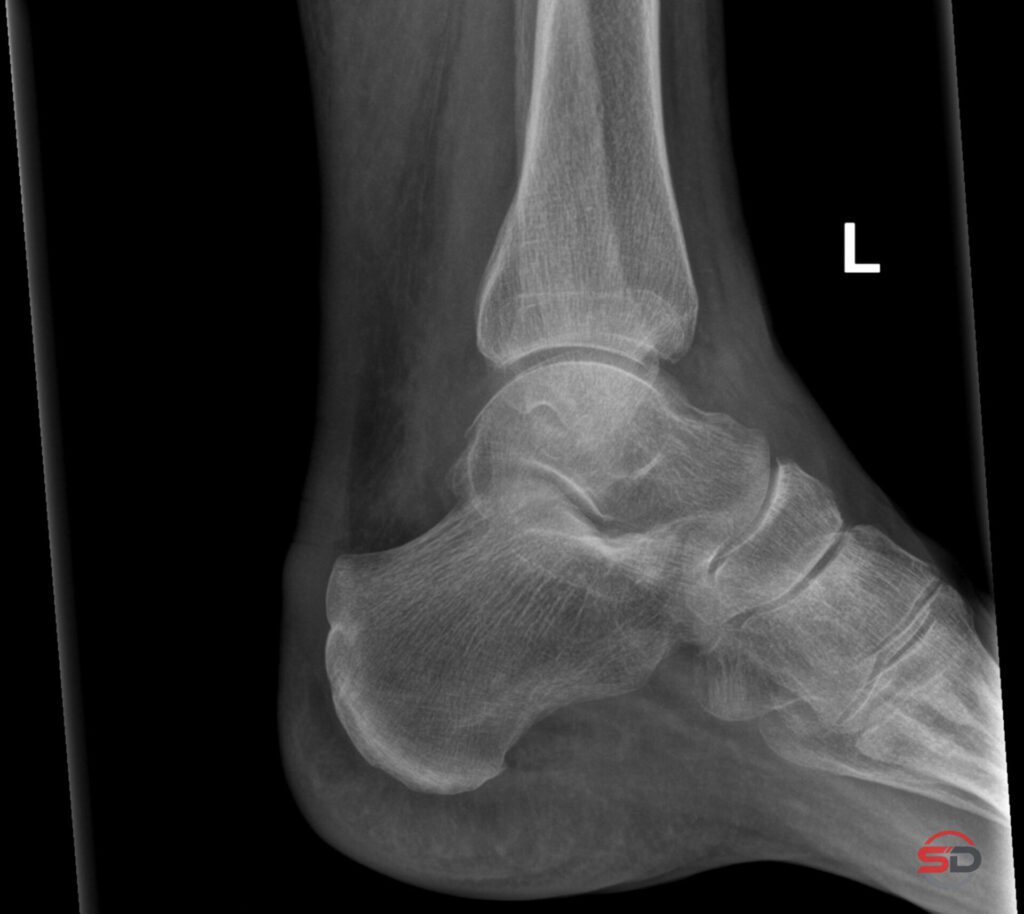

Knochentumoren im Röntgenbild erkennen – was ist wichtig?

Knochentumoren im Röntgenbild – was ist wichtig? Ein Zufallsbefund im konventionellen Röntgenbild gehört zum klinischen Alltag. Eine unerwartete Knochenläsion […]